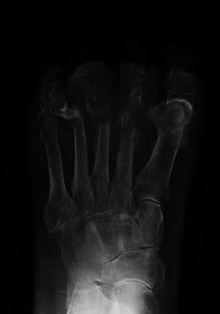

| Osteomyelitis of the 1st toe | |